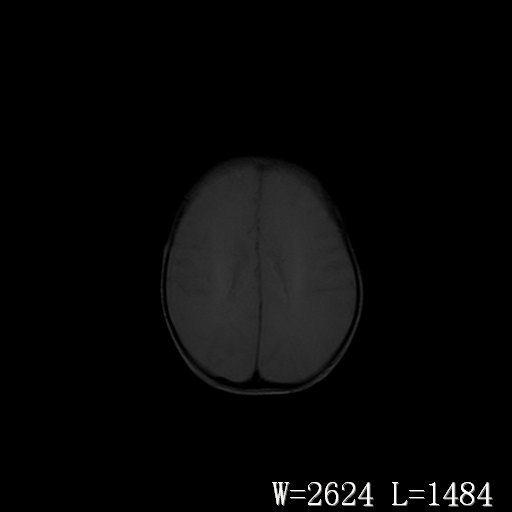

男,4天,发复抽搐1天。

新生儿正常颅脑

hie?

脑干形态欠规则,信号增高,不知怎么解释?

脑干背侧面t1高信号是,新生儿正常已经髓鞘化好的部位